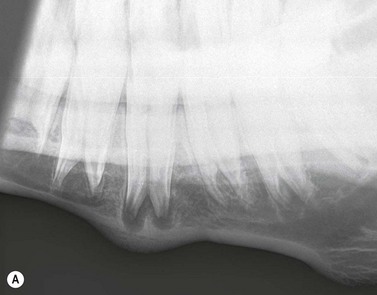

Intra-oral oblique projections (Figs 13.1913.20)

These projections, where a flexible film package or cassette is placed into the oral cavity, represent a modification of the bisecting angle technique used widely in human dental imaging. They have the advantages that there is no superimposition of structures from the contralateral side of the skull, and can also give good detail of the interdental bone and alveolar crest region. However, in the author’s experience, these projections can be difficult to obtain in standing sedated horses, due to difficulties keeping the film in place within the oral cavity.

The use of human dental film packs4 or of improvised cassettes made of vinyl7 or heavy-duty black polythene1 has been described for intra-oral projections in horses. Pre-packed human dental film is often only large enough to image one or two cheek teeth on each radiograph, and this is a major disadvantage, particularly because the affected tooth is not commonly identified prior to the radiographic examination. Improvised cassettes can be made into a suitable shape for the equine oral cavity (circa 10 × 25 cm) by cutting down film and card-mounted intensifying screen(s) before double wrapping them in closely fitting, light-proof bags e.g., of heavy-duty black polythene, and sealing the edges with light-proof adhesive tape.1 The disadvantages of this system include the time taken to prepare the above materials, poor film/screen contact and the need for wet processing of films.

A self-retaining, full-mouth speculum is used to open the mouth of the heavily sedated or anesthetized horse, and the film is placed in the oral cavity, parallel to the hard palate (Fig. 13.19). If using a small sized film, it must be placed at the level of the tooth of interest. For teeth of mature or older horses, the X-ray beam is directed at an angle of 50°–60° to the horizontal, but to examine the longer reserve crowns of young horses, increased incident angles (70°–80°) are required (Fig. 13.19). The centering point is somewhere between the level of the facial crest and up to 6 cm dorsal to the facial crest, depending on the length of the tooth being radiographed i.e., in younger horses, a more dorsal centering point is required compared to aged horses with short reserve crowns.